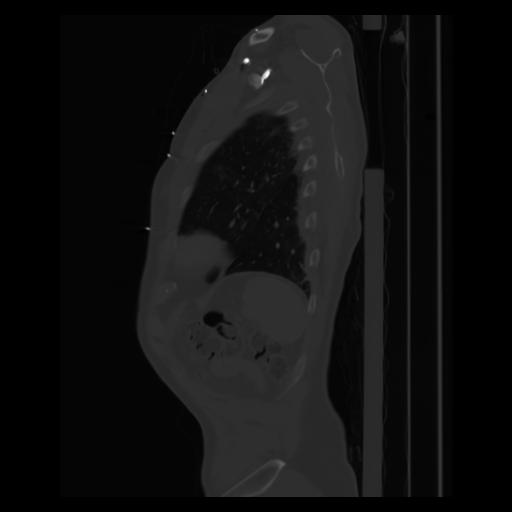

30 CUERPO,CE,Sagittal,3.000,CUERPO,Sagittal,